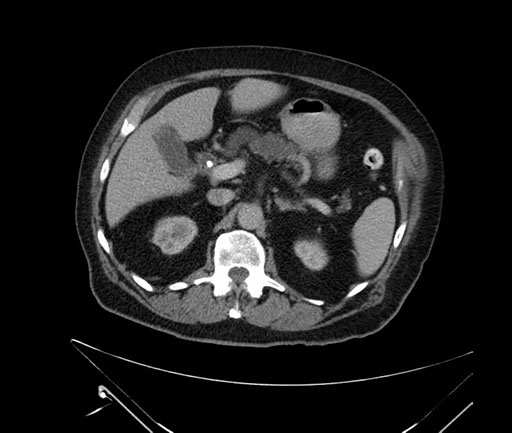

Imaging Analysis

Look through the patient's CT scan to identify any areas of concern for the necessary procedure.

Based on your CT findings, which issue(s) would give reason for "planned slowing down moment(s)" in this case?